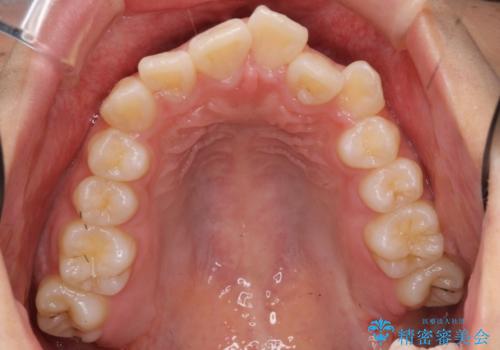

- 前歯のがたがたを主訴に来院。

口元も下げたいとのことでした。

成人式の1年前から矯正をはじめ、成人式前に上の前歯の装置を一時的にとりました。

一時的に装置を取ることで、多少治療期間が伸びましたが、それでも、2年かからずに外すことができました。